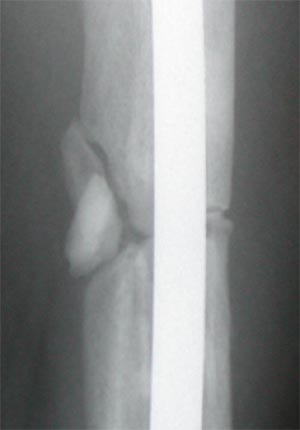

X-Rays Of My Broken Femur - Lateral Closeup

Week 21

Week 27